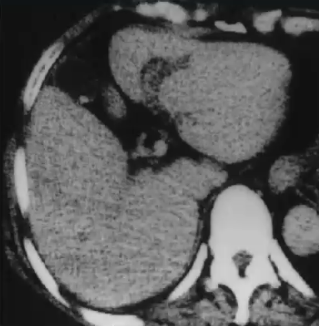

❖ 肝硬化伴门脉高压症:多发性肝胆道周围囊肿

❖ 尽管胆道周围囊肿通常被认为是无临床症状,囊性扩张似乎是梗阻性黄疸进展的原因